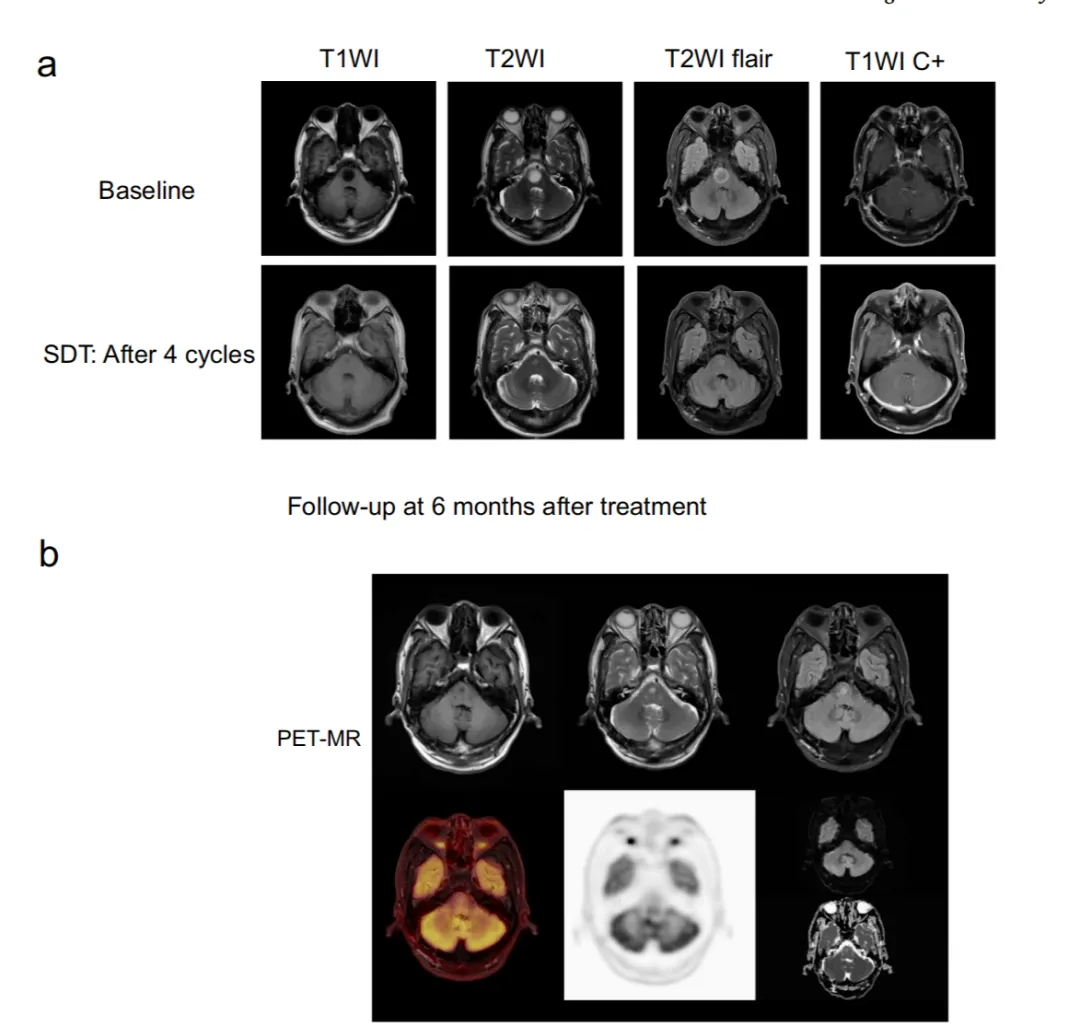

在I期试验确认安全性的基础上,团队进一步开展了更具挑战性的IIa期研究,专门针对高级别脑干胶质瘤,并设立了同期对照。该研究将接受“声动力疗法+标准Stupp方案(放化疗)”的24名患者(SDT组),与同期仅接受“标准Stupp方案”的39名患者(对照组)进行比较,结果发表于《Photodiagnosis and Photodynamic Therapy》。安全性再次验证:联合治疗组的不良事件发生率与对照组无显著差异,且绝大多数为1-2级,再次证实了该方案叠加在标准治疗之上的安全性。疗效数据全面胜出:肿瘤反应更好:SDT组的客观缓解率(ORR,即肿瘤显著缩小的比例)达到33.3%,显著高于对照组的10.3%。研究报告中甚至出现了1例达到完全缓解的病例,其MRI影像显示肿瘤近乎完全消除,增强了治疗反应的证据。病情控制更持久:SDT组病情得到控制的持续时间中位数(DDC)为10.1个月,也显著长于对照组的6.8个月。生存期显现延长趋势:SDT组的中位无进展生存期(11.5个月)和总生存期(15.6个月)均优于对照组(6.0个月和10.8个月)。其中,6个月和1年的无进展生存率显著更高。生活质量改善更快:治疗后1个月,SDT组患者的体力状况评分(KPS)改善程度显著优于对照组,意味着患者的生活质量在短期内能得到更快提升。“剂量依赖性”效应——治疗越多,获益越大:研究中的一个重要发现是,接受超过2个周期声动力治疗的患者,其中位总生存期达到了 20.9个月,显著优于接受≤2个周期治疗的患者(14.9个月)。这清晰地表明,足程、规范的治疗能为患者带来更大的生存获益。

图6. 1例高级别患者达到完全缓解的病例,其PET-MRI影像显示肿瘤近乎完全消除。